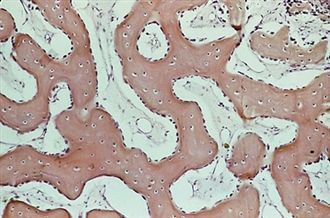

Tejido Conectivo: Óseo (esponjoso)

Tejido Conectivo: óseo (compacto)

Tejido conectivo: cartilaginoso (hialino)